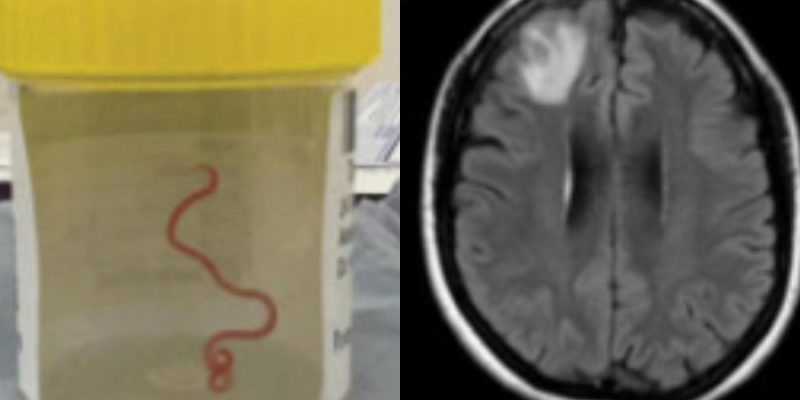

«Usé pinzas para sujetar tumores y saqué algo que definitivamente no esperaba: un cordel lineal y serpenteante. Y el médico asistente dijo: ‘¿Es una arteria?’, porque eso es lo que parecía. Pero yo le dije: ‘No es una arteria. No estamos cerca de ninguna arteria’. Y me di cuenta de que se movía e inmediatamente dije, ‘por favor, ¡sácalo de mis pinzas!’. Así que lo pusimos rápidamente en un recipiente de patología y era un gusano que se movía vigorosamente», contó.

La criatura encontrada en el cerebro de la mujer se trataba de una la larva de un gusano parasitario autóctono de Australia, llamado Ophidascaris robertsi, el cual normalmente se encuentra presente en serpientes o en pitones, pero que hasta ahora no se conocía ningún caso en humanos.

El médico infectólogo Sanjaya Senanayake, coautor de la publicación reciente, señaló que estaba de turno en el hospital en junio del año pasado, cuando le informaron sobre el caso. En un principio se pensaba que la paciente podía tener un tumor o cáncer: «Esta paciente había sido tratada por una enfermedad misteriosa que, en última instancia, pensamos que era una afección inmunológica porque no habíamos sido capaces de encontrar un parásito y, de la nada, apareció este gran bulto en la parte frontal de su cerebro», destacó Senanayake.